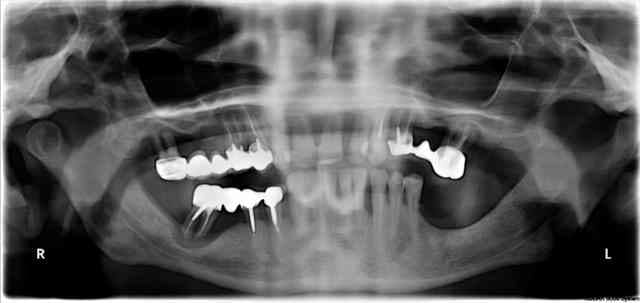

regardes cette radio panoramique par exemple...

petit indice, le "bientôt mci", à ton avis, il reste quoi actuellement (j'ai fait du "ménage")

Je viens de recevoir une pano ton avis.

En te remerciant pour tes commentaires Alain

Il est inutile de te rappeler que la perte d'attache parodontale ne peut être supérieure à la perte osseuse. Or sur le cas de Posit la perte osseuse, qui est très globalement de profil horizontal, ne semble pas excéder les 2/3 de la longueur radiculaire. De plus les quelques lésions infraosseuses présentent ne me semble pas ingérables par ttt parodontal adapté.

La seule interrogation concerne les lésions endodontiques éventuelles mais dans tous les cas si il y en a, elles n'ont pas "soufflé" les corticales.

Donc je réitère ma remarque et trouve que le choix d'extraction dans un tel cas est excessif.

En ce qui concerne la mobilité dentaire, elle est loin d'être étonnante vu le manque de calage postérieur et n'est en aucun cas un critère extractionnel.